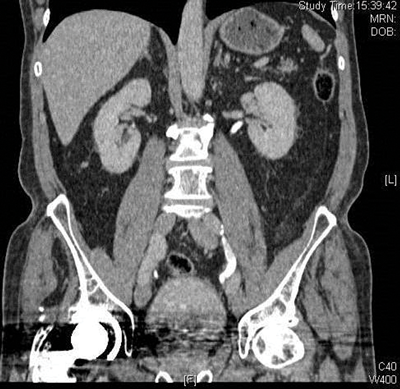

The collecting systems and ureters should be opacified on the excretory phase of CT urogram and adequate distension and opacification of the ureter and pelvicalyceal system are vital when evaluating the urothelium. Filling defects can be difficult to appreciate on abdominal windows and subtle filling defects are more clearly seen on bone window settings. This can allow ureteric neoplasms to be distinguished from other causes of filling defects. Figure 4 shows an example of a filling defect in the left ureter that is more clearly defined on bone windows compared with abdominal windows. This was a female patient who presented with cyclic pain and was found on biopsy to have endometriosis in the left ureter.

Figure 4a: Abdominal windows filling defect.

Figure 4b: Bone windows filling defect.